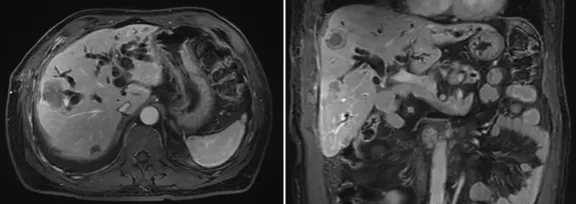

影像學檢查結(jié)果

image.png

右肺炎癥不能排除,請結(jié)合臨床。右側(cè)少量胸腔積液